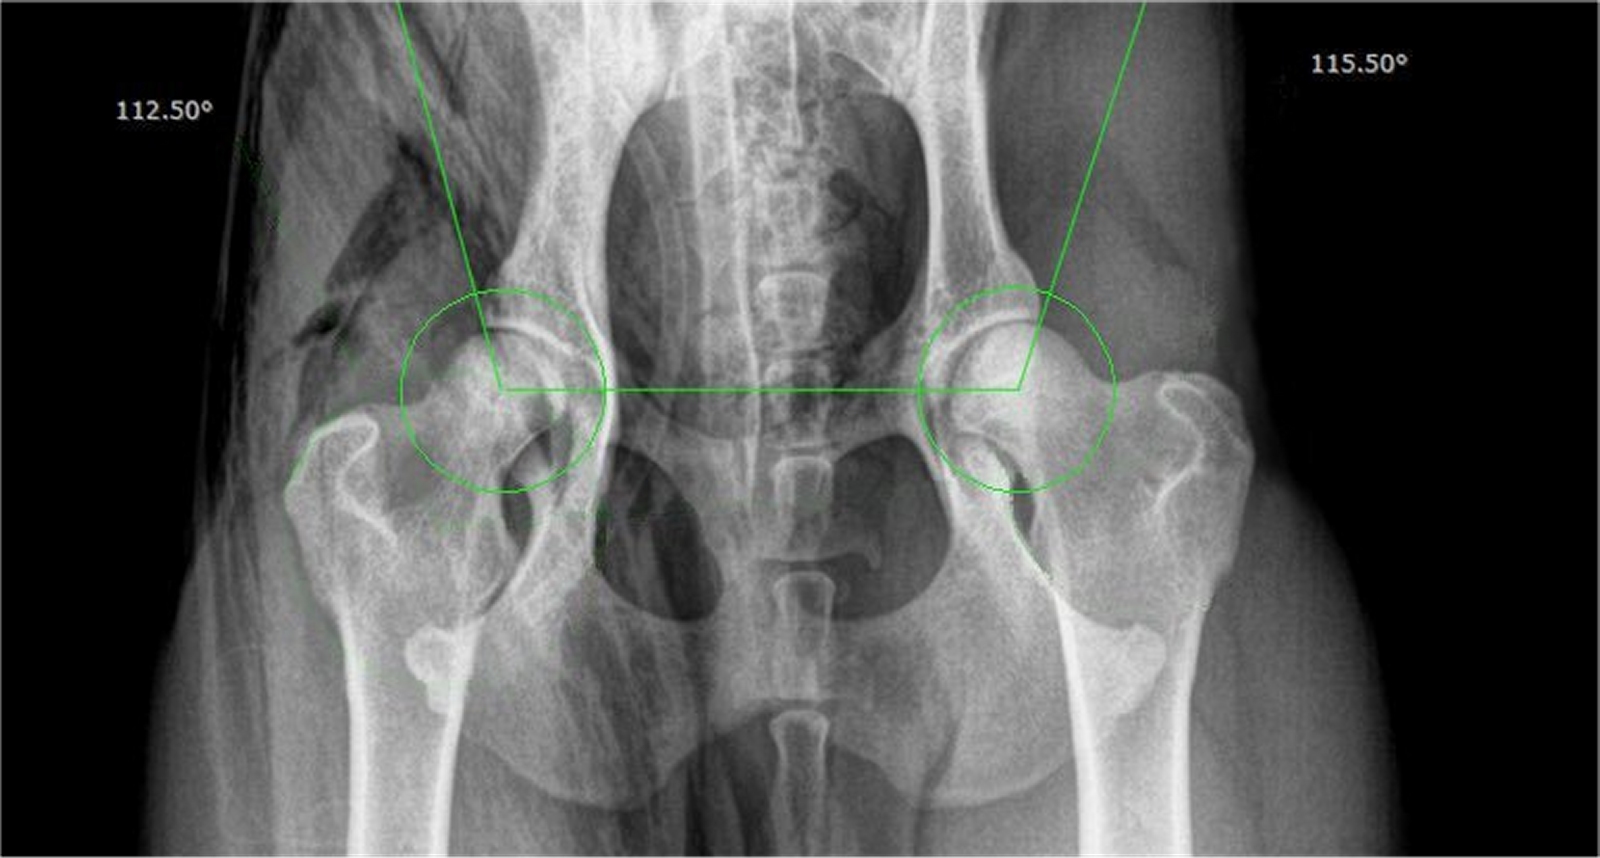

Chihuahua Jumba veel mannelijke hormonen had in zijn lijf; met